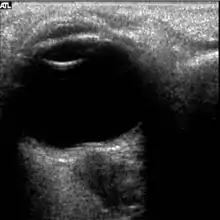

The astronauts affected by long term visual changes and prolonged intracranial hypertension have all been male, and SOS may explain this because in men, the sternocleidomastoid muscle is typically thicker than in women and may contribute to more compression. The reason that SOS does not occur in all individuals may be related to anatomic variations in the internal jugular vein. Ultrasound study has shown that in some individuals, the internal jugular vein is located in a more lateral position to Zone I compression, and therefore not as much compression will occur, allowing continued blood flow.

Intracranial pressure (ICP) needs to be directly measured before and after long duration flights to determine if microgravity causes the increased ICP. On the ground, lumbar puncture is the standard method of measuring cerebral spinal fluid pressure and ICP,[6][44] but this carries additional risk in-flight.[4] NASA is determining how to correlate ground-based MRI with inflight ultrasound[4] and other methods of measuring ICP in space is currently being investigated.[44]

There are different approaches to non-invasive intracranial pressure measurement, which include ultrasound "time-of-flight" techniques, transcranial Doppler, methods based on acoustic properties of the cranial bones, EEG, MRI, tympanic membrane displacement, oto-acoustic emission, ophthalmodynamometry, ultrasound measurements of optic nerve sheath diameter, and Two-Depth Transorbital Doppler. Most of the approaches are "correlation based". Such approaches can not measure an absolute ICP value in mmHg or other pressure units because of the need for individual patient specific calibration. Calibration needs non-invasive "gold standard" ICP meter which does not exists. Non-invasive absolute intracranial pressure value meter, based on ultrasonic Two-Depth Transorbital Doppler technology, has been shown to be accurate and precise in clinical settings and prospective clinical studies. Analysis of the 171 simultaneous paired recordings of non-invasive ICP and the "gold standard" invasive CSF pressure on 110 neurological patients and TBI patients showed good accuracy for the non-invasive method as indicated by the low mean systematic error (0.12 mmHg; confidence level (CL) = 0.98). The method also showed high precision as indicated by the low standard deviation (SD) of the random errors (SD = 2.19 mmHg; CL = 0.98).[46] This measurement method and technique (the only non-invasive ICP measurement technique which already received EU CE Mark approval) eliminates the main limiting problem of all other non-successful "correlation based" approaches to non-invasive ICP absolute value measurement – the need of calibration to the individual patient.[47]